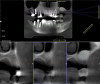

Dental implants are a predictable treatment option for the replacement of missing teeth. However, adjunctive surgical procedures may be required prior to implant placement. Sinus augmentation is indicated for cases in which deficient vertical bone height in the posterior region of the maxilla prevents dental implant placement. If inadequate residual bone height is present coronal to the maxillary sinus, the lateral sinus augmentation technique is recommended because it allows for the placement of larger volumes of graft material as well as greater access and visibility. In this technique, an osteotomy is made over the lateral sinus wall using rotary burs or a piezoelectric tip, taking care to keep the sinus mucosa intact (Figure 1). The sinus mucosa is then elevated (Figure 2), and a bone graft material is placed (Figure 3). Once healed, a significant increase in height and volume of bone can be seen radiographically (Figure 4 and Figure 5).

(4.) Preoperative cone-beam computed tomography (CBCT) image of the tooth No. 14 site prior to lateral sinus augmentation.

Figure 4

(5.) Postoperative CBCT image of the tooth No. 14 site taken 6 months after lateral sinus augmentation.

Figure 5